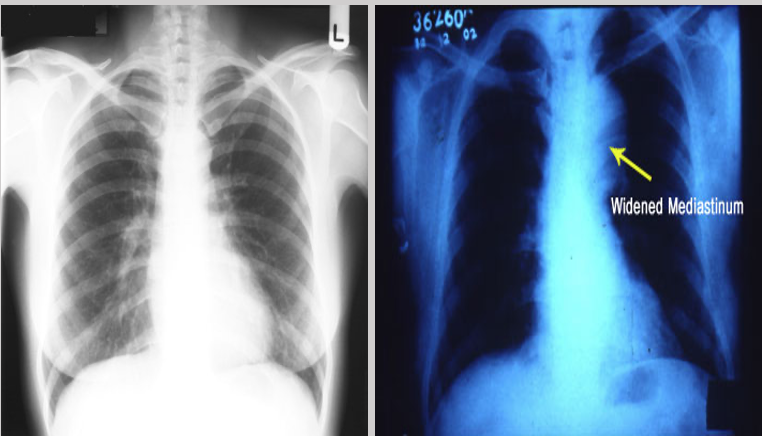

What does this chest x-ray refer to

Thoracic Aneurysm

Widened mediastinum on CXR